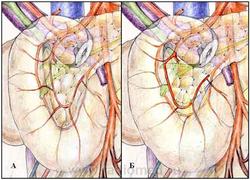

Весьма вариабельно взаимоотношение нижнегоризонтальной и нисходящей частей ДПК (дистальнее бульбодуоденального сфинктера) и головки поджелудочной железы. При этом были обнаружены крайние варианты нормальных анатомических взаимоотношений этих образований: ДПК широко и плотно фиксирована к головке поджелудочной железы, особенно в зоне большого дуоденального сосочка, за счет сращения фиброзной капсулы поджелудочной железы и собственной фасции ДПК, при этом передняя и задняя панкреатодуоденальные артерии максимально широко отстоят друг от друга (рис. 2.1, «А»); ДПК имеет собственную брыжейку, являющуюся дупликатурой пред- и позадиподжелудочных фасций (фасциальной капсулы поджелудочной железы), в которой проходят питающие кишку ветви от передней и задней поджелудочно-двенадцатиперстных артериальных и венозных дуг (рис. 2.1, «Б»).

Рисунок 2.1. Крайние варианты взаимоотношения нижнегоризонтальной и нисходящей части двенадцатиперстной кишки и головки поджелудочной железы.

А - ДПК плотно фиксирована к головке поджелудочной железы, передняя и задняя панкреатодуоденальные артерии максимально широко отстоят друг от друга;

Б - ДПК имеет собственную брыжейку, передняя и задняя панкреатодуоденальные артерии максимально сближены.